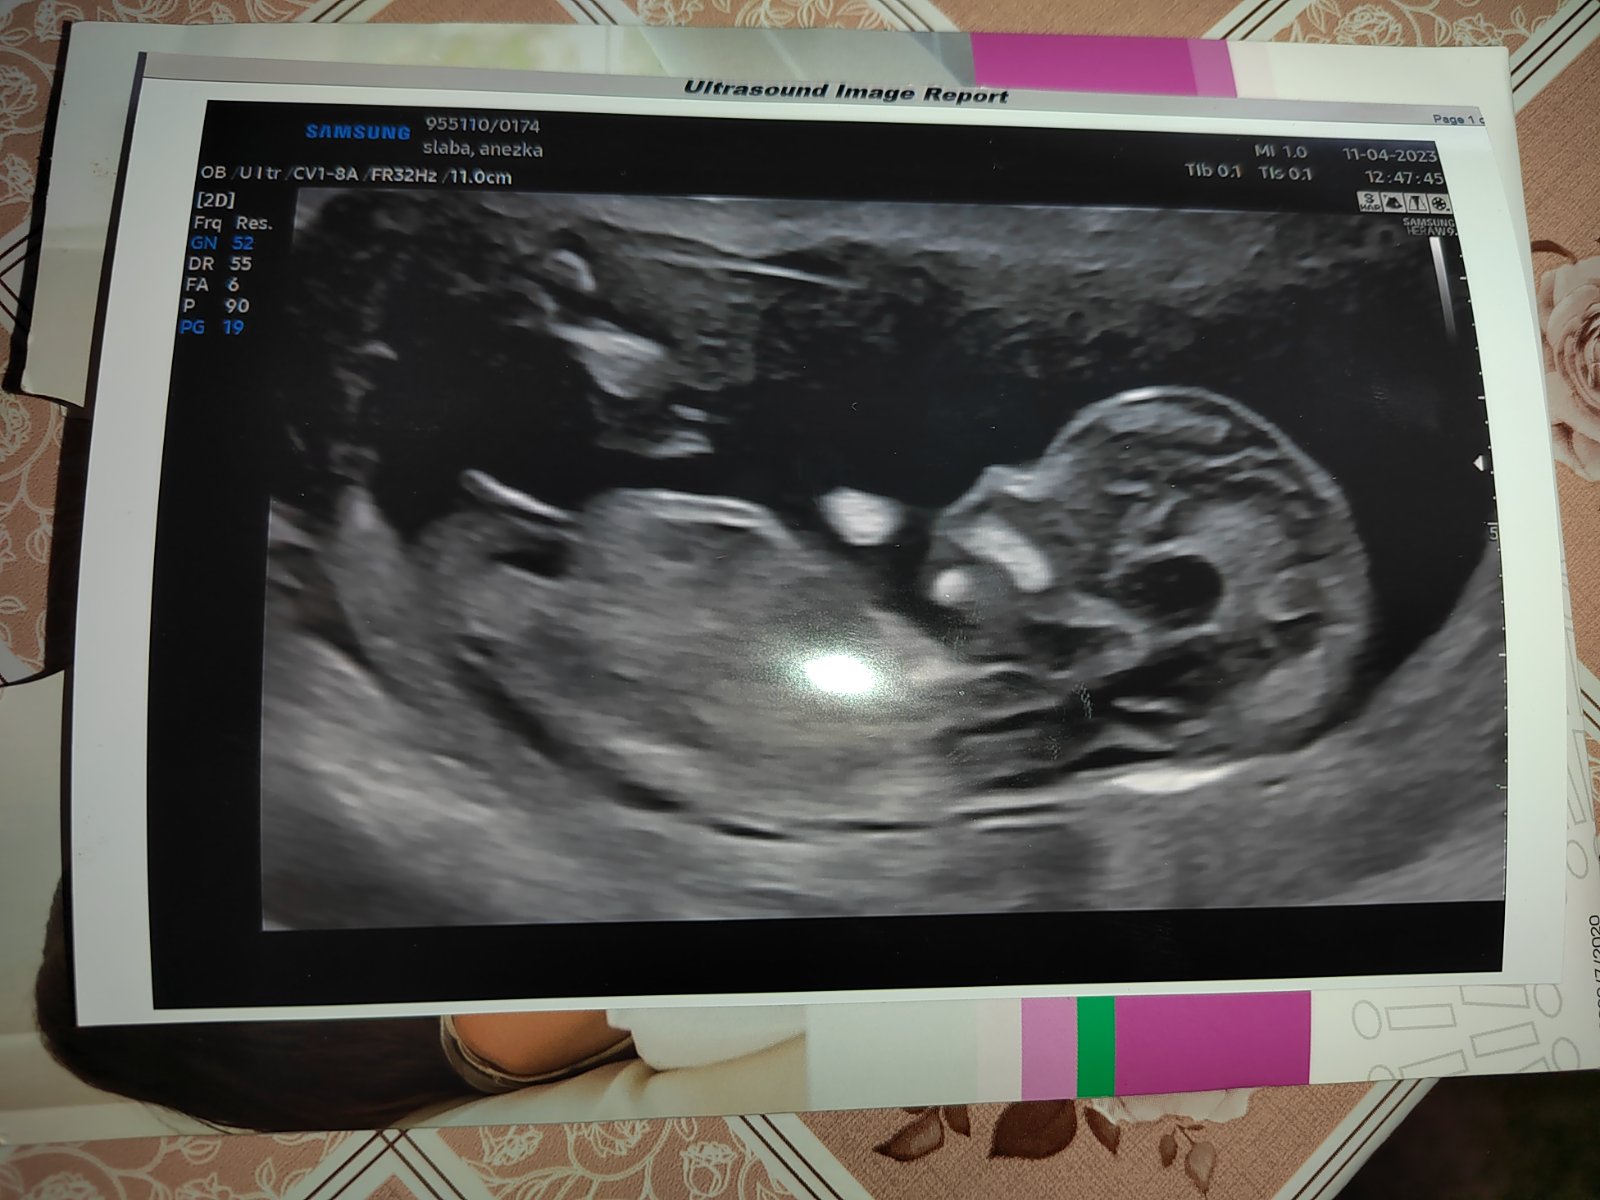

Dobrý den, oživuji diskuzi ❤️ 11tt, je to jen screenshot z videa které jsem si natočila na mobil, tak bůh ví, zda jsem to cvakla v dobrou chvíli a není to klamavé 😄 Co myslíte? Do prenatalu jdeme až 6.11. a já mám pocit že prasknu nedočkavostí, jsem zvědavec hrozný 🙈 Toť otázka - pohlavní hrbolek, nebo jsou to kulky, nebo konec kostrče? Co myslíte, jen tak pro srandu? Přáli bychom si holku, ale kdyz jsem videla prvni pohyby na UTZ v 11+1, tak jsem si uvědomila že ať bude co bude, budu mimi milovat uplne stejne bez rozdílu ❤️ Je to mazec!!

@xkbkbx tady hrbolek bohužel vidět nejde. Možná holka, jestli je hrbolek to co si myslím, ale neupinala bych se na to 😁